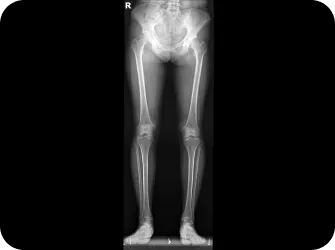

나도 혹시? 미리 체크해보는 자가진단 테스트

허리디스크 자가진단 체크리스트

• 다리 길이에 차이가 있다.

똑바로 누운 상태에서 양쪽 다리 길이를 잽니다.

(다리를 일부러 비뚤게 놓거나 자세가 나쁘면 정확한 측정이 곤란)

한 쪽 다리가 짧다면 골반이 비뚤어졌거나 척추가 불안정한 상태입니다.